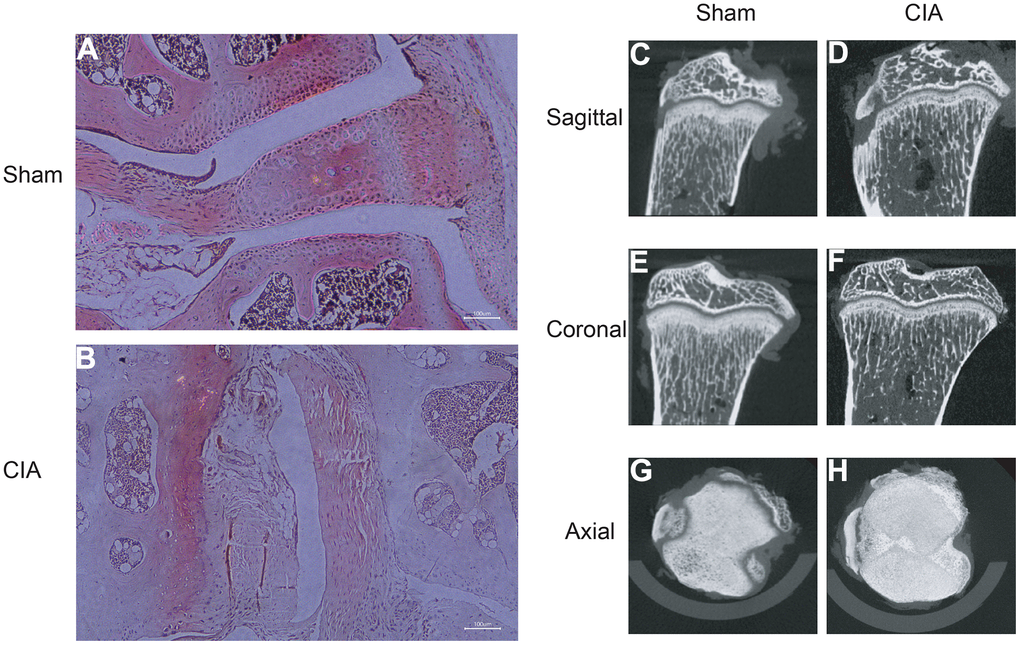

Building CIA mouse model and validating diagnostic biomarkers

To verify the expression of the diagnostic biomarkers AKR1C3, MCEE, POLE4, and PFKM in RA, we developed a CIA mouse model. We obtained and stained knee joint sections of two successfully modeled groups of mice, and found that in comparison with the Sham group mice (Figure 8A), the histological analysis of the knee joint sections of CIA mice (Figure 8B) showed a significant up-regulation in the level of inflammation and immune cell infiltration, with crushed cartilage boundary. Using bone structure micro-CT, we scanned and detected the knee joints of both groups of mice. Sham group mice showed a smooth bone surface and relatively intact joint structure (Figure 8C, 8E, 8G), while CIA group mice showed bone and cartilage erosion, irregular bone surface structure, and severe osteoporosis (Figure 8D, 8F, 8H). These results confirm the successful modeling of RA in CIA mice. Furthermore, immunofluorescence results of the knee joints of the two groups of mice showed that AKR1C3, MCEE, and POLE4 were highly expressed in the CIA group mice compared to the Sham group, while PFKM was expressed at a lower level (Figure 9A–9D). This result is similar to what we obtained from clinical tissues. These results further demonstrate the high value of these four diagnostic biomarkers in the research of RA diagnosis and treatment.

Figure 8. HE staining of mouse joints and micro-CT imaging of mouse joints. (A) HE staining of joints in the Sham group mice. (B) HE staining of joints in the CIA group mice. (C–H) Micro-CT imaging of joints in the Sham and CIA group mice.